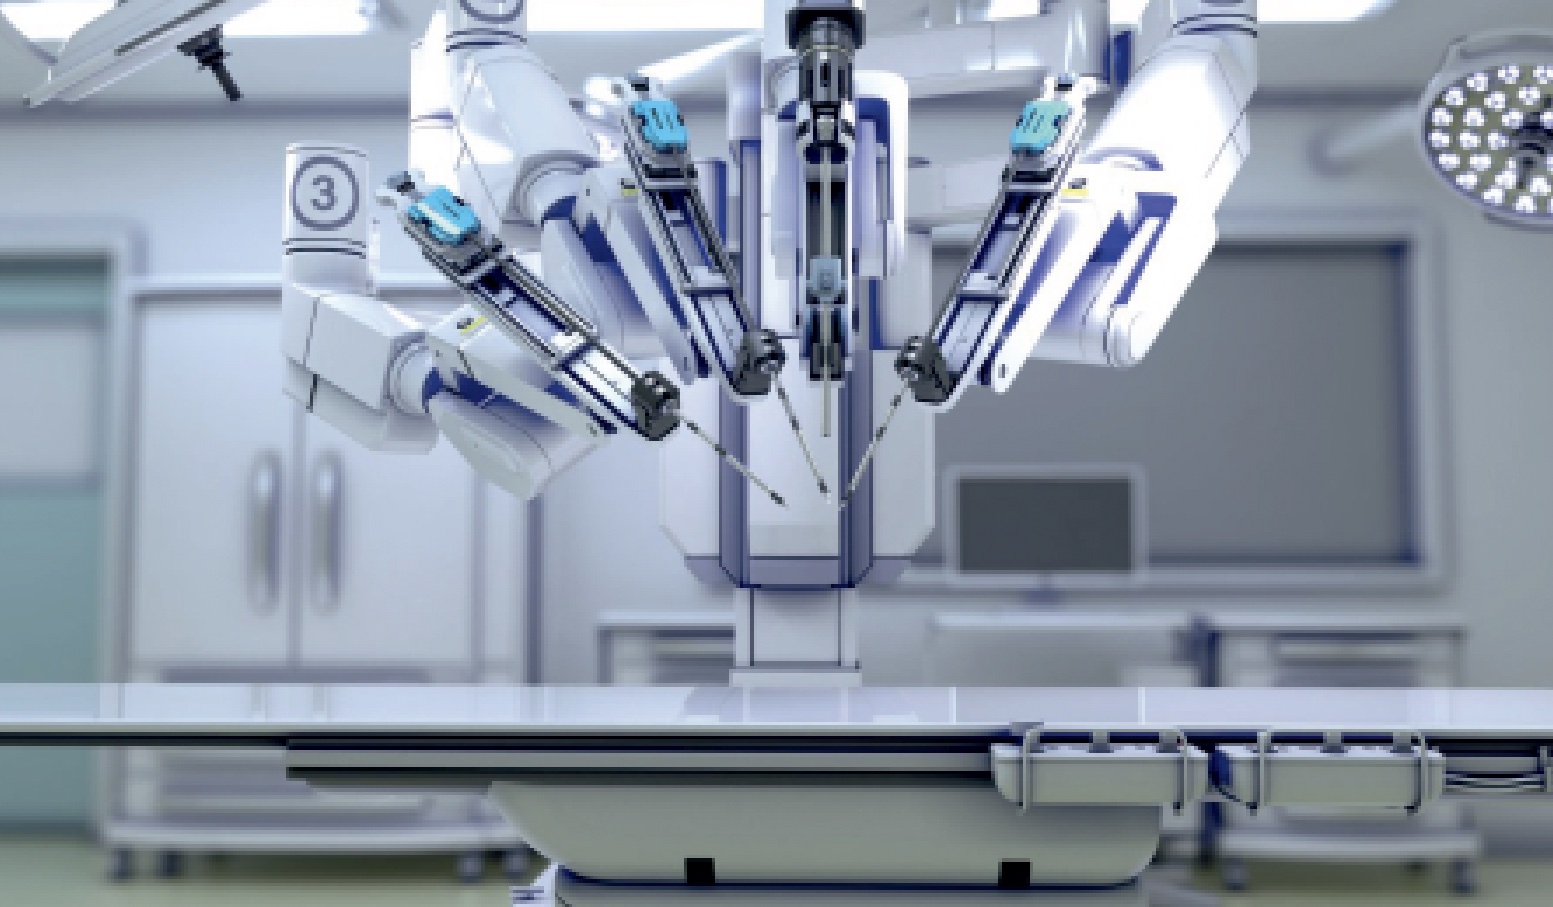

What happens during Robotic Surgery? Will the robot operate me?

Robotic hip replacement surgery is performed by the surgeon with the help of the robot. The surgeon will open up the hip, make a real time map of the deformed/ damaged surface ends of the bones and then using the robot, plan the surgery. Once the surgery is virtually performed on the robotic screen, the robotic burrs are used to burr off/ shave off the surface and tissue balance is achieved throughout the range of movement, an artificial implant is fitted on the surface. The wound is closed and dressing applied. You are then shifted to the recovery room!